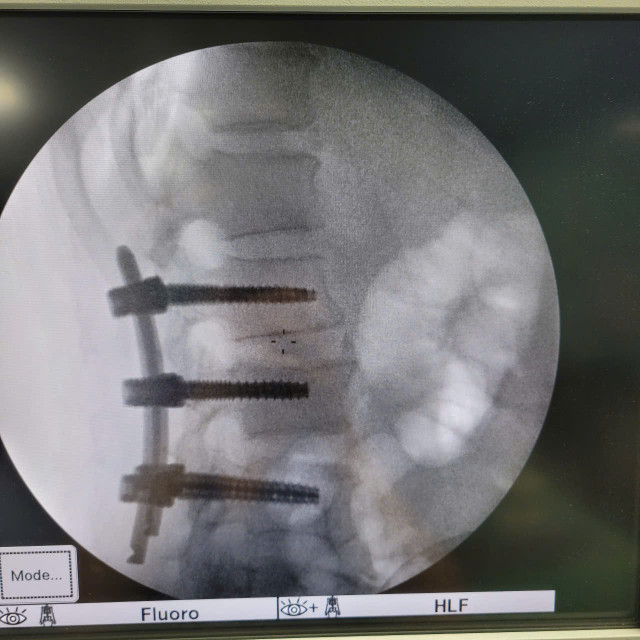

Các bác sĩ Khoa Ngoại Thần kinh – Chấn thương Chỉnh hình, Bệnh viện Hữu Nghị đã triển khai thành công kỹ thuật mới, phẫu thuật bắt vít cột sống qua da ít xâm lấn cho bệnh nhân nam 59 tuổi bị chấn thương cột sống, vỡ đốt sống L2 gây mất vững.

Sử dụng hệ thống máy C-arm, dẫn đường hình ảnh (navigation) để đặt vít chính xác tuyệt đối, tránh tổn thương tủy sống và rễ thần kinh.